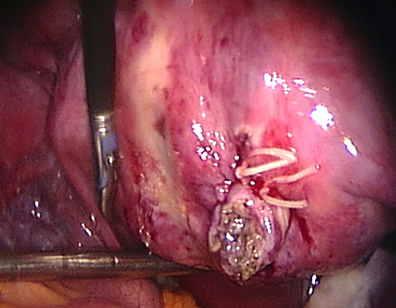

Intraoperative photos

A uterus with a benign tumour or fibroid is shown in a patient interested in further pregnancies.

The uterus is being reconstructed with sutures applied laparoscopically.